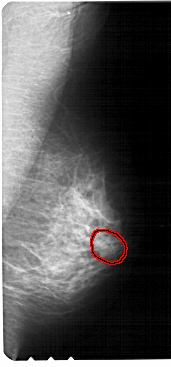

FILE: A_1320_1.RIGHT_MLO.OVERLAY

TOTAL_ABNORMALITIES 1

ABNORMALITY 1

LESION_TYPE CALCIFICATION TYPE AMORPHOUS DISTRIBUTION CLUSTERED

ASSESSMENT 4

SUBTLETY 3

PATHOLOGY BENIGN

TOTAL_OUTLINES 1

BOUNDARY